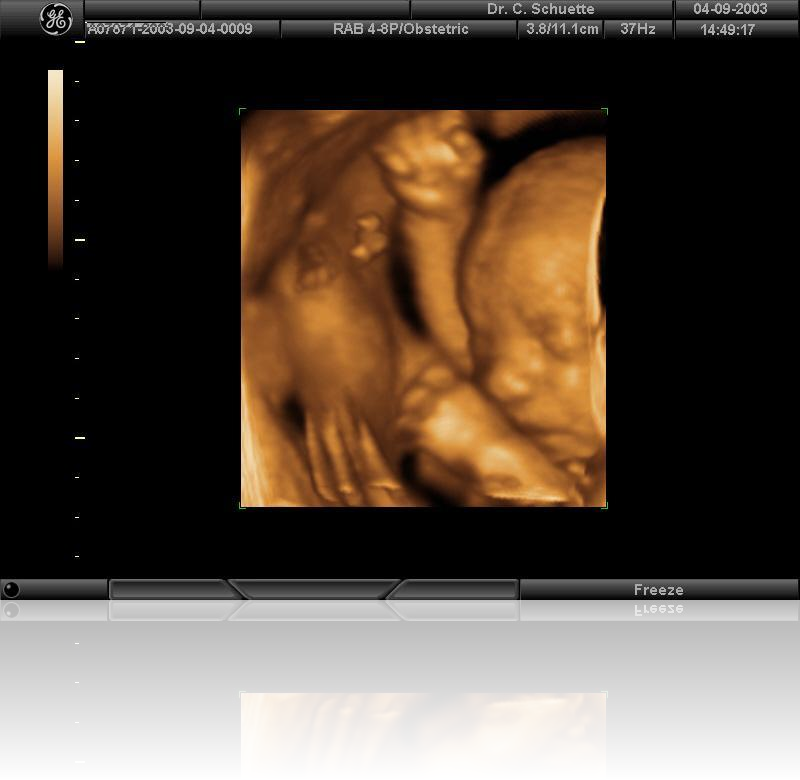

• 3D / 4D Ultraschall ermöglicht verblüffend fotorealistische Bilder, sogar Gestik und Mimik können in bewegten Sequenzen (4D) festgehalten werden